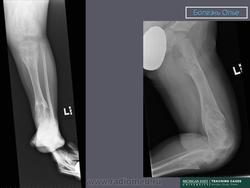

ОЛЛЬЕ СИНДРОМ (описан французским хирургом L. Ollier, 1830–1900; синоним – энхондроматоз, остеохондроматоз) – системное нарушение развития скелета, при котором на ранних этапах эмбриогенеза нарушается трансформация хряща в костную ткань; в растущей кости сохраняются очаги необызвествленной хрящевой ткани, что приводит к деформации и укорочению костей. Возможно поражение 1 (монооссальная форма заболевания), 2–3 (олигооссальная форма заболевания), 4 и более (полиоссальная форма заболевания) костей; поражаются преимущественно метафизы длинных трубчатых костей, фаланги пальцев, тазовые кости. Проявления заболевания возникают в возрасте 2–10 лет и зависят от локализации и тяжести процесса. Изменения обычно двусторонние, но асимметричные. При локализации процесса в нижних конечностях наблюдаются хромота, перекос таза, вальгусная или варусная деформация и прогрессирующее укорочение ног. При поражении верхних конечностей характерны лучевая или локтевая косорукость, выраженная деформация пальцев. Возможны патологические переломы. Нередко наблюдается малигнизация с развитием хондросаркомы. В редких случаях сочетается с гемангиомами мягких тканей (синдром Мафуччи). Диагноз уточняют при рентгенологическом исследовании, выявляющем четкие очаги овального или веерообразного просветления в метафизах длинных трубчатых костей. Тип наследования – предположительно аутосомно-доминантный. Лечение: выравнивание длины нижних конечностей с помощью ортопедической обуви, в случае выраженных деформаций показана хирургическая коррекция.

Клиническая картина. Заболевание выявляется в раннем детском возрасте, с началом ходьбы появляются деформации костей, хромота, прогрессирующее укорочение конечностей. Нередко первым проявлением болезни служат патологические переломы измененной кости; гемангиомы (при синдроме Мафуччи).Рентгенологически трубчатые кости умеренно или значительно укорочены, эпиметафизы булавовидно расширены, вздуты; в метафизах определяются очаги просветления неоднородной структуры.

Болезнь Олье.

Клиническая картина. Заболевание выявляется в раннем детском возрасте, с началом ходьбы появляются деформации костей, хромота, прогрессирующее укорочение конечностей. Нередко первым проявлением болезни служат патологические переломы измененной кости; гемангиомы (при синдроме Мафуччи). Рентгенологически трубчатые кости умеренно или значительно укорочены, эпиметафизы булавовидно расширены, вздуты; в метафизах определяются очаги просветления неоднородной структуры.